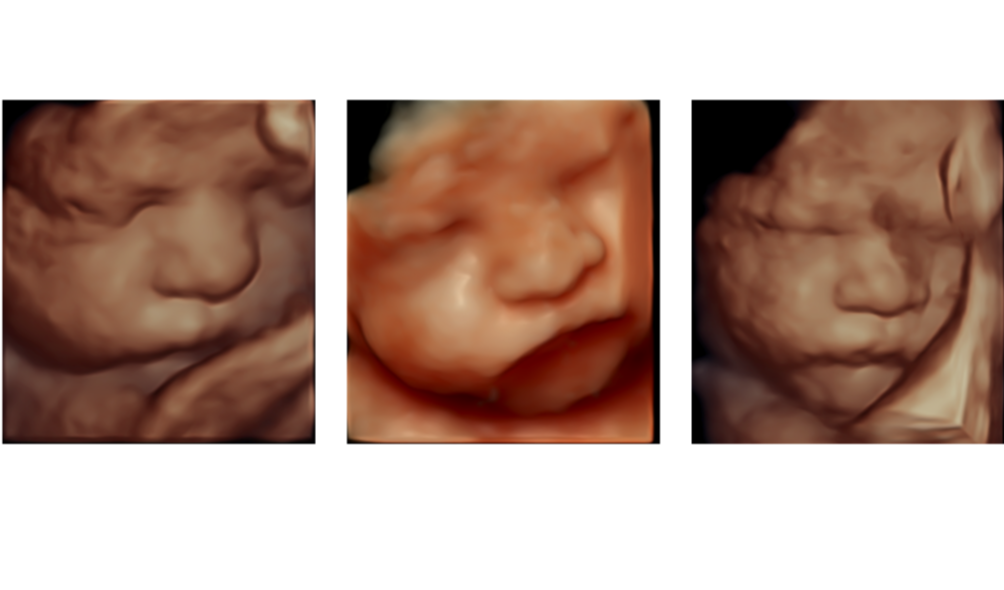

We offer a full range of obstetric and gynaecological ultrasound services, performed by specialist sonographers with state-of-the-art equipment and reports delivered by a Maternal Fetal Medicine specialist.

A detailed anatomy scan of your baby, assessing all major organs and structures. This is one of the most important scans during pregnancy, checking your baby's development and growth in detail. -